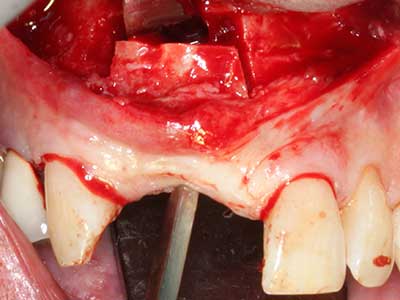

Indicazione: incisione ossea

Il tessuto osseo non è semplicemente una struttura minerale, ma contiene anche una percentuale significativa di fibre di collagene. Ciò significa che non possiede solo una buona forza di compressione, ma anche un certo livello di flessibilità che è possibile sfruttare durante l'esecuzione degli accrescimenti di osso. Nella procedura di espansione classica con incisione ossea, la cresta alveolare atrofizzata viene incisa longitudinalmente ed espansa con cautela dopo aver raggiunto una profondità di osteotomia adeguata (figg. 13-16), idealmente senza una sostanziale rimozione del periostio (Brugnami, Caiazzo et al. 2014, Stricker, Fleiner et al. 2014). I sistemi a piastra e vite con distanza di espansione incrementale si sono dimostrati efficaci nella separazione delle due lamelle ossee restando al di sotto della soglia di frattura. In generale, sono richieste larghezze dell'osso residuo di almeno 3-4 mm (Chiapasco, Zaniboni et al. 2006) per garantire un'adeguata flessibilità e una copertura sufficiente dell'osso per gli impianti futuri. Se necessario, un'osteotomia di rilascio verticale su uno o più lati può migliorare la flessibilità. Una combinazione con ulteriori tecniche di accrescimento, in particolare dal lato buccale, è stata descritta come un'alternativa alla tecnica classica.

La procedura di incisione è particolarmente atraumatica e non comporta una perdita significativa di dimensione durante l'utilizzo delle seghe piezoelettriche, così come non si notano differenze rilevanti tra impianti in mandibole incise e impianti in una cresta alveolare senza deficit osseo (Chiapasco, Zaniboni et al. 2006, Danza, Guidi et al. 2009). Una sufficiente irrigazione continua è essenziale, tuttavia, in particolare con incisione profonda e localmente ristretta, per prevenire la sollecitazione termica nelle regioni apicali dell'osteotomia.